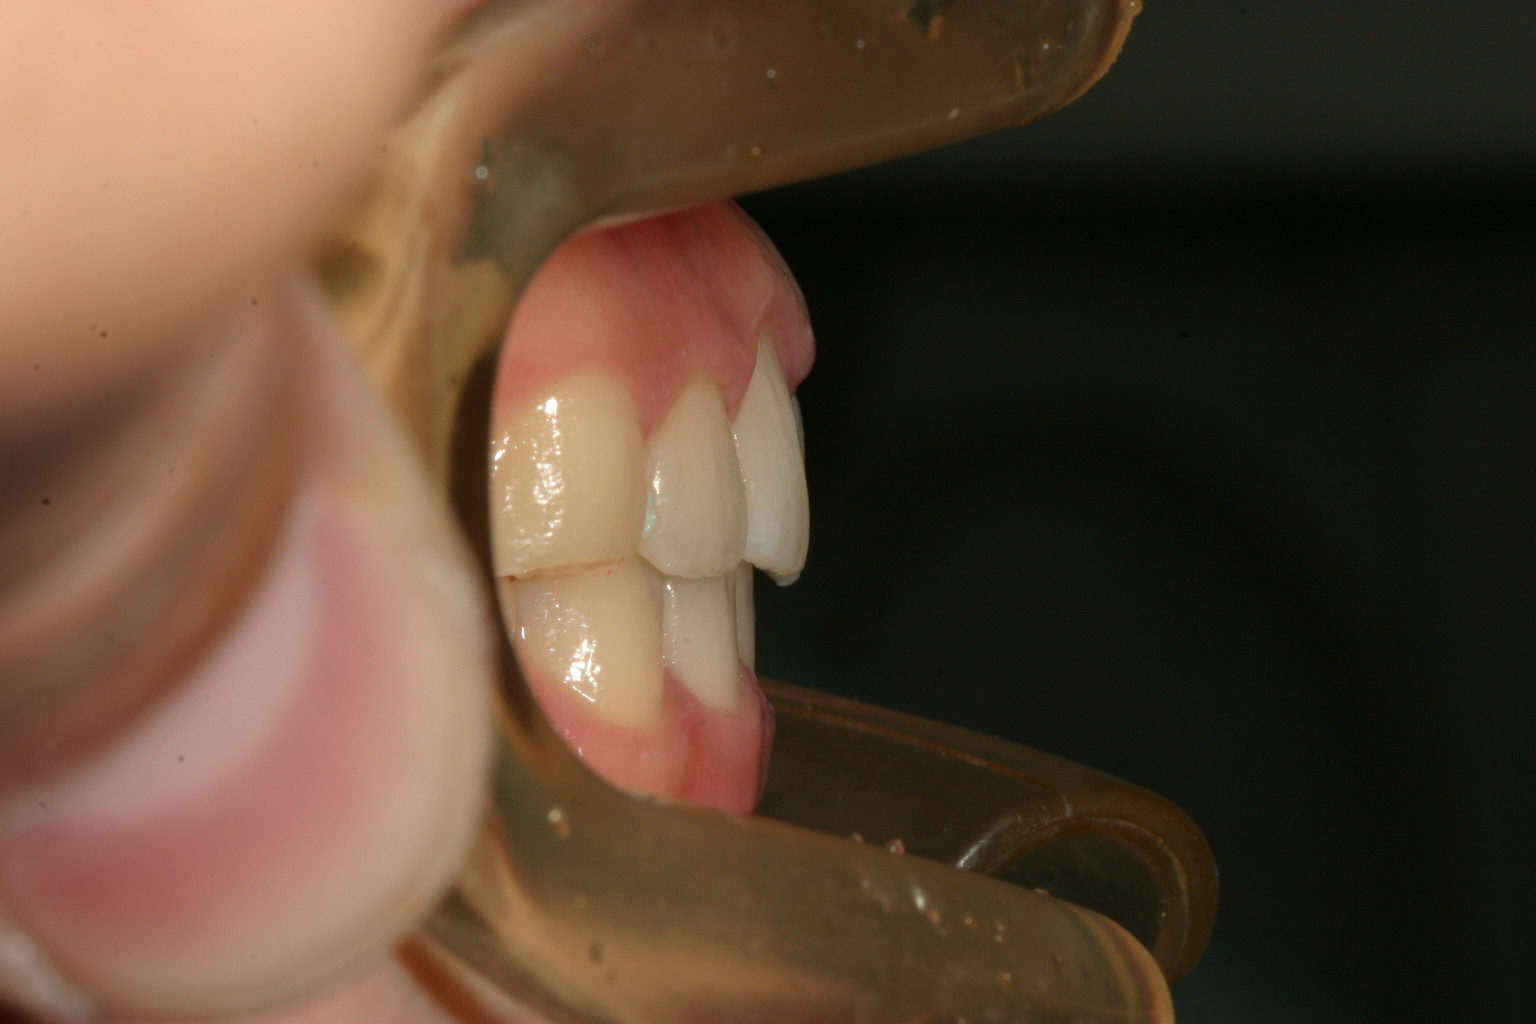

アーチが尖ってるのが気になります。

少し上下の前後差が気になります。